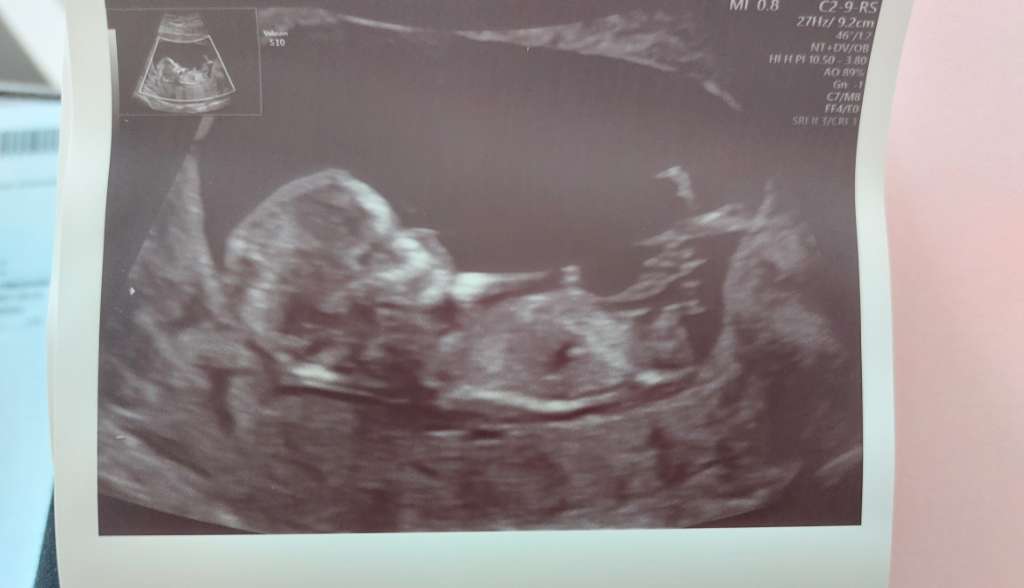

Już po badaniach prenatalnych. Ryzyko trisomii dość niskie bo 1 na 11500 dla zespołu Downa, a dla pozostałych poniżej 1 na 20000. Ogólnie dzidzia szalała dzisiaj w brzuchu, cały czas podskakiwała i wierciła się 😁. Płci na razie nie pokazała ale może 21-ego czerwca na kolejnej wizycie uda nam się podejrzeć. Ma 6cm obecnie, serduszko dalej wszystko dobrze. Ogólnie powiedziała lekarka że z USG na razie wszystko pięknie wygląda 🥰. Ale widok jak szaleje i się rusza wzruszający! Wcześniej się tak nie wzruszałam jak dzisiaj 😊.